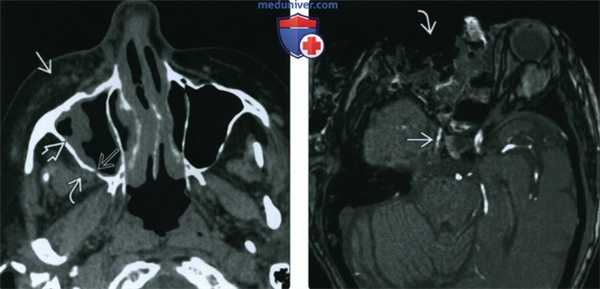

(Слева) При аксиальной КТ без КУ у пациента с диабетом определяется относительно легкое поражение слизистой оболочки правой верхнечелюстной пазухи. Обращает на себя внимание замещение предчелюстной и ретроантральной жировой клетчатки инфильтративным мягкотканным компонентом (подтвержденный ОИГРС, Mucor). Определяется незначительное нарушение целостности костей задней стенки верхнечелюстной пазухи.

(Справа) При аксиальной MPA (ТОР) после экзентерации правой орбиты определяется неравномерное сегментарное сужение просвета кавернозного сегмента правой внутренней сонной артерии вследствие ОИГРС (Mucor).

(Слева) На аксиальной КТ с КУ у пациента с инвазивным мукормикозом левой верхнечелюстной и решетчатой пазухи определяется тромбоз кавернозного синуса и кавернозного сегмента внутренней сонной артерии (ВСА) слева. Обратите внимание, что правая ВСА заполняется контрастом.

(Справа) На аксиальной MPT (Т1 ВИ С+ FS) у этого же пациента определяется распространенное поражение левого кавернозного синуса, а также окклюзия интракраниального сегмента ВСА, обусловленная инвазивной грибковой инфекцией левого кавернозного синуса.